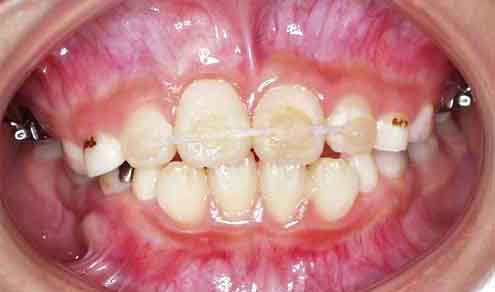

治療開始5ヶ月後